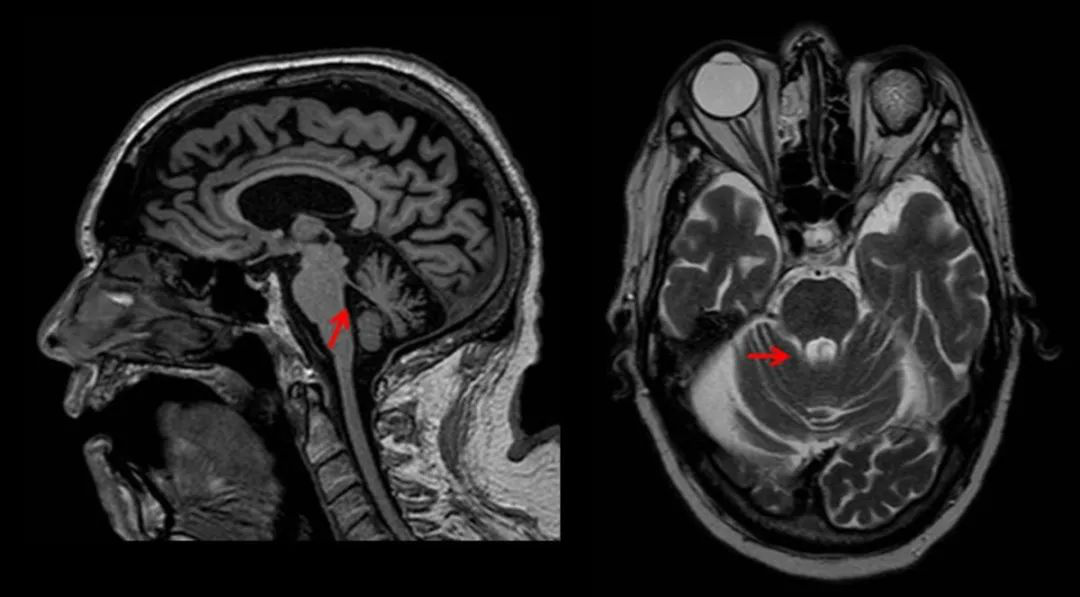

進行性核上性麻痹(PSP):是另一種神經(jīng)系統(tǒng)退行性疾病,其特征是眼球運動異常(核上垂直凝視性麻痹)、輕度癡呆和姿勢不穩(wěn),起病隱匿,多見于 60 歲。其他常見癥狀有構(gòu)音障礙、吞咽困難、對稱性關(guān)節(jié)僵硬綜合征、頸部張力障礙和蹣跚步態(tài)。

PSP 的 MR 常出現(xiàn):特征是中腦和被蓋萎縮;在矢狀位中,中腦被蓋萎縮形似「蜂鳥」;在軸位中,中腦萎縮,頂蓋和大腦腳保留形似「米老鼠」。